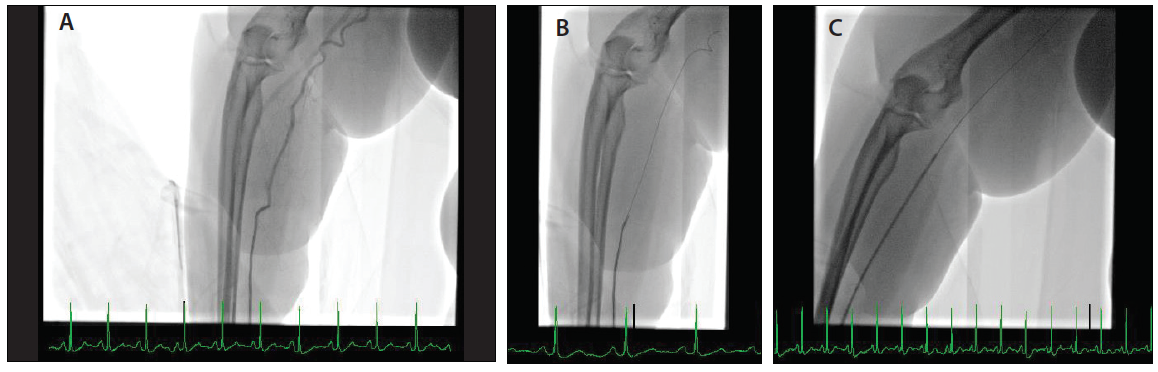

Using a 6-F Railway™ sheathless access system and a 6-F Judkins right (JR) 4 Launcher® guide (Medtronic), the right TRA was obtained (Figure 2A). After getting direct guide catheter access in the RA, the Railway™ dilator was removed and the catheter was connected to the manifold using a Y-connector. Vasodilator cocktail (nitroglycerin 100 mcg + verapamil 2.5 mg) was injected through the manifold (Figure 2B). RA angiography was performed because of difficulty in advancing a 0.035-inch J wire, which showed severe tortuosity in the RA originating from the axillary artery (Figure 3A). A 0.018-inch V-18™ ControlWire™ (Boston Scientific Corporation) was advanced through the tortuosity(Figure 3B). A JR 4 guide catheter was advanced using a 0.018-inch Railway™ dilator without any resistance (Figure 3C) under direct fluoroscopic guidance to the right subclavian artery. The 0.018-inch wire and Railway™ dilator were removed. The JR 4 guide was cannulated in the right coronary artery (RCA). The mid-RCA subtotal occlusion (Figure 4A) was treated with a 1.5- X 20-mm balloon, followed by 3- X 15-mm and 3- X 15-mm Cobra PzF™ stents (CeloNova BioSciences, Inc.) to treat the 95% to 99% stenosis in the mid-RCA and 70% stenosis in the mid/distal RCA, respectively, with a very good final angiographic result (Figure 4B).

Figure 2. A 6-F, 0.018-inch Railway™ dilator is preloaded with a guide catheter, and direct guide catheter access is obtained over a 0.018-inch access wire in the RA (A). An example of a guide catheter in the distal RA after direct catheter access, and an intra-arterial vasodilator cocktail is injected using the manifold (B).